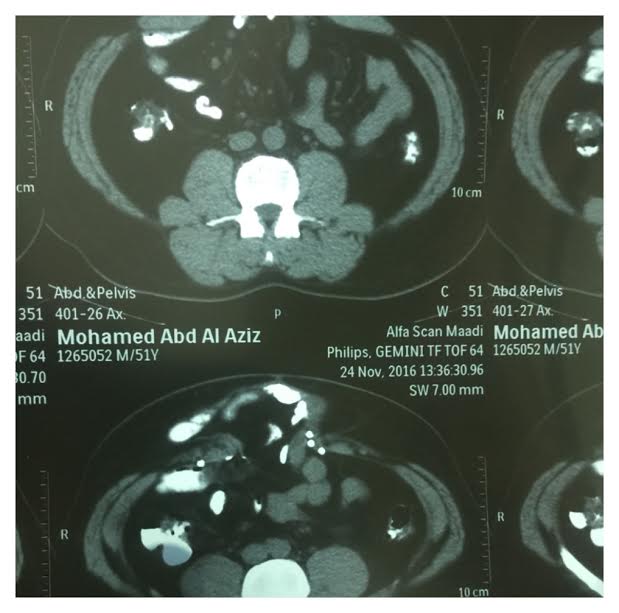

وتابع أنه تمت الموافقة على عمل العملية بعد دراسة الوضع بشكل جيد وبالصور المقطعية وتمت العملية عبر ثلاث مراحل.

المرحلة الأولى إغلاق من داخل البطن، حيث وضعت شبكة جراحية مخصصة لذلك، وتعتبر هذه الخطوة كافية لإصلاح الفتق، ثم المرحلة الثانية -كانت الأصعب- وهي فصل مكونات جدار البطن ثم إعادة تشكيلها لإغلاق فتحت جدار البطن، تسمى بالإنكليزية component séparation technique، وتمت المرحلة الثانية بشكل جيد ثم المرحلة الثالثة وهو تثبيت جدار البطن من الخارج بوضع شبكة.